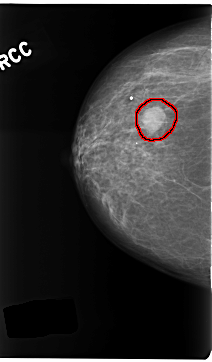

C_0278_1.RIGHT_CC

FILE: C_0278_1.RIGHT_CC.OVERLAY

TOTAL_ABNORMALITIES 1

ABNORMALITY 1

LESION_TYPE MASS SHAPE ROUND MARGINS CIRCUMSCRIBED

ASSESSMENT 4

SUBTLETY 5

PATHOLOGY BENIGN

TOTAL_OUTLINES 1

BOUNDARY